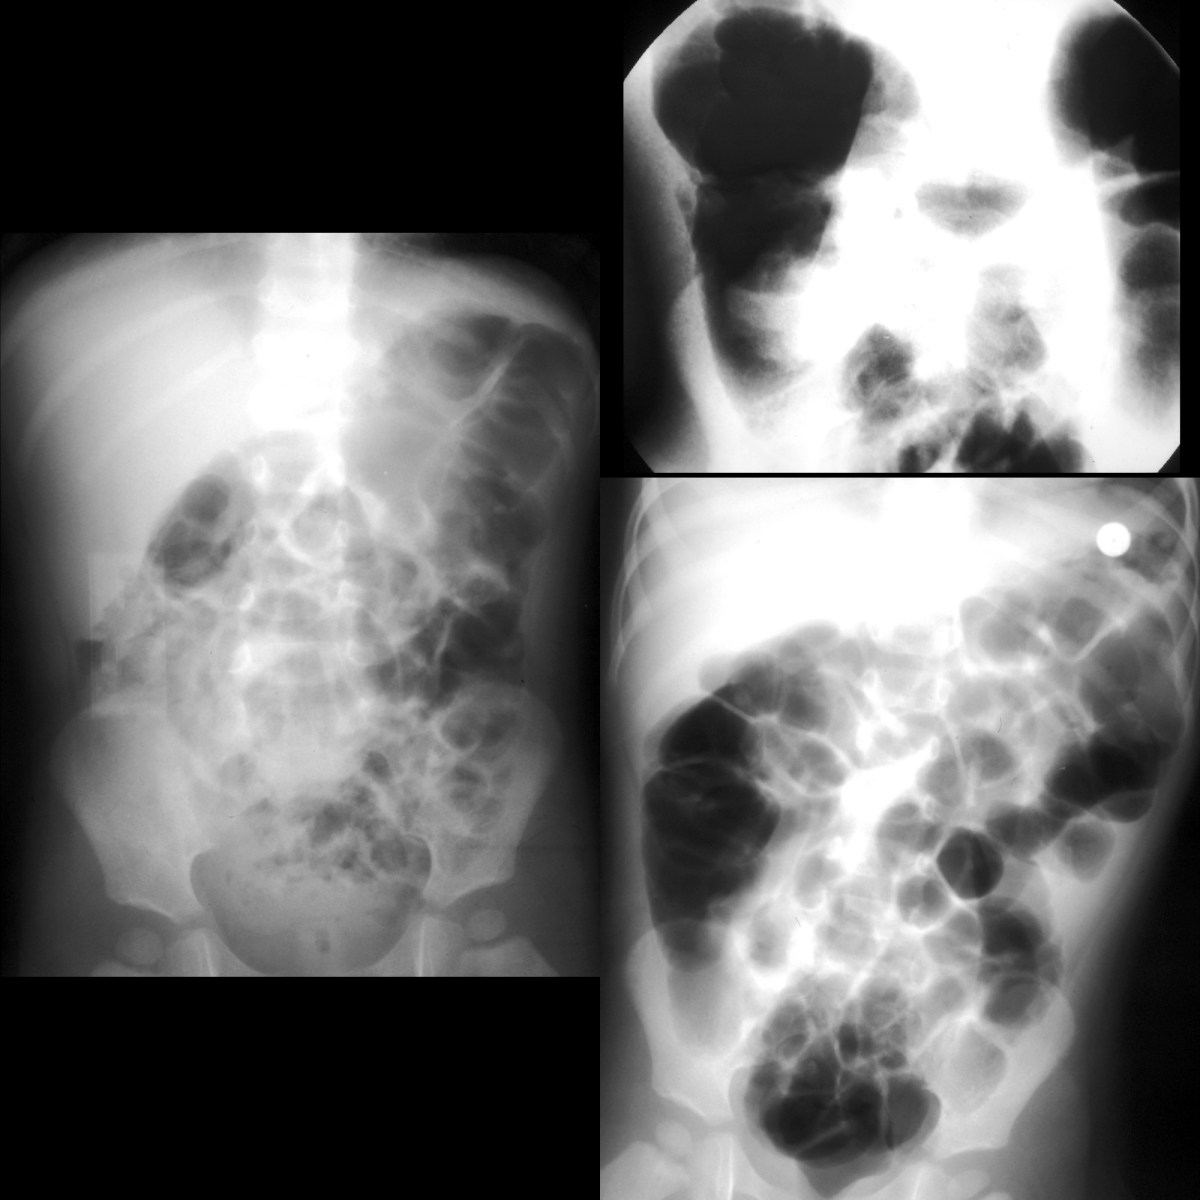

From pediatricimaging.org

Toddler with bilious vomiting, crampy abdominal pain, bloody stools Bloody Stools Toddler — blood in a toddler's stool is usually due to an underlying condition. check if you're bleeding from the bottom. Blood on your toilet paper. You might be bleeding from the bottom if you have: — seeing blood in your child's bowel movements (sometimes known as rectal bleeding or bloody stools) can. — rectal bleeding in. Bloody Stools Toddler.